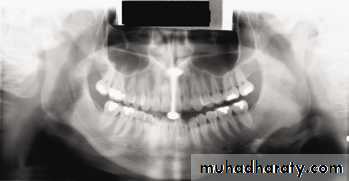

In a good panoramic radiograph:

The mandible is “U” shaped.The condyles are positioned about equal distance from the inside edges of the image and 1⁄3 of the way down from the top edge of the image.

The occlusal plane exhibits a slight curve or “smile line,” upwards.

The roots of the maxillary and mandibular anterior teeth are readily visible with minimal distortion.

Magnification is equal on both sides of the midline.

1, Mandibular condyle. 2, Articular eminence. 3, Coronoid process of mandible superimposed on zygomatic arch. 4, Posterior wall of maxillary sinus. 5, Posterior wall of zygomatic process of maxilla. 6, Hard palate. 7, Nasal septum. 8, Tip of nose. 9, Dorsum of tongue. 10, Hyoid superimposed over inferior border of mandible. 11, Inferior border of maxillary sinus. 12, Image of cervical spine. 13, Medial border of maxillary sinus. 14, Infraorbital canal. 15, Infraorbital rim. 16, Pterygomaxillary fissure. 17, Anterior border of the pterygoid plates. 18, Lateral pterygoid plate superimposed over soft palate and coronoid process of mandible. 19, Ear lobe. 20, Inferior border of mandibular canal. 21, Mental foramen. 22, Posterior wall of nasopharynx. 23, Inferior border of mandible superimposed from opposite side. 24, Soft palate over mandibular foramen of mandible.